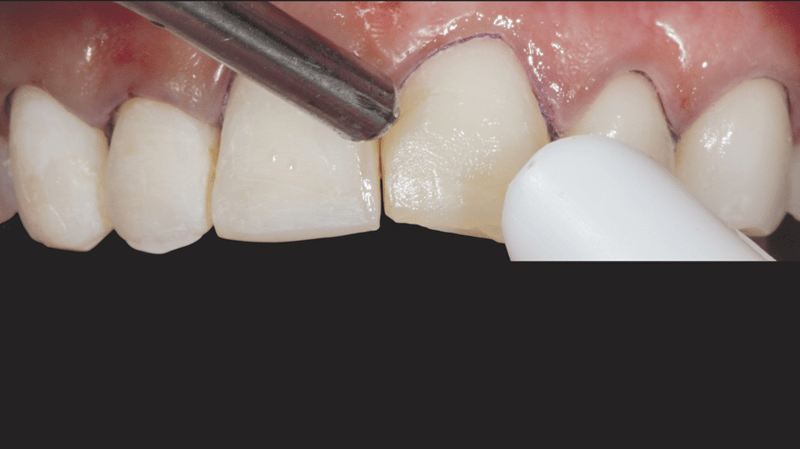

- Veneerseparatie: Met een mesje #12 en een separeerzaag werden de veneers vervolgens zorgvuldig van elkaar gescheiden, voor een preciezere afwerking.